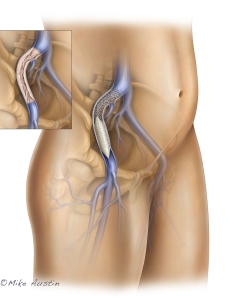

Welcome to my Patient and Professional Marketing page, where I harness the power of anatomical illustrations to educate and empower both patients and medical professionals. My unique approach combines artistry and education to convey complex surgical procedures and the utilization of medical devices in an easily understandable manner.